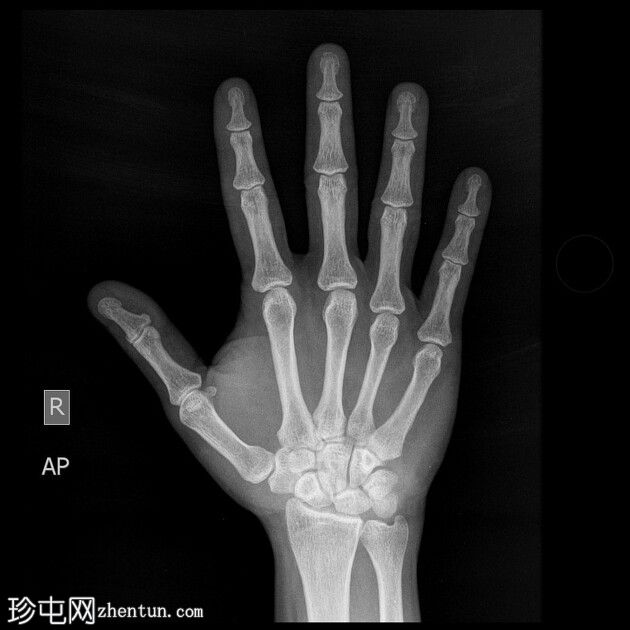

患者一天前因40公斤重的沙井事故,右手食指和中指遭受挤压伤。

X光片

正面

右手X光片显示中指远端指骨末端失去正常的光滑轮廓,皮质轮廓不规则,提示远端骨折畸形。骨折在斜位片上更容易被看到,并伴有轻度移位和周围软组织肿胀。

X光片结果显示中指远端指骨末端骨折,皮质轮廓不规则,正常轮廓丧失,可能由直接创伤引起,例如重物撞击或挤压伤。